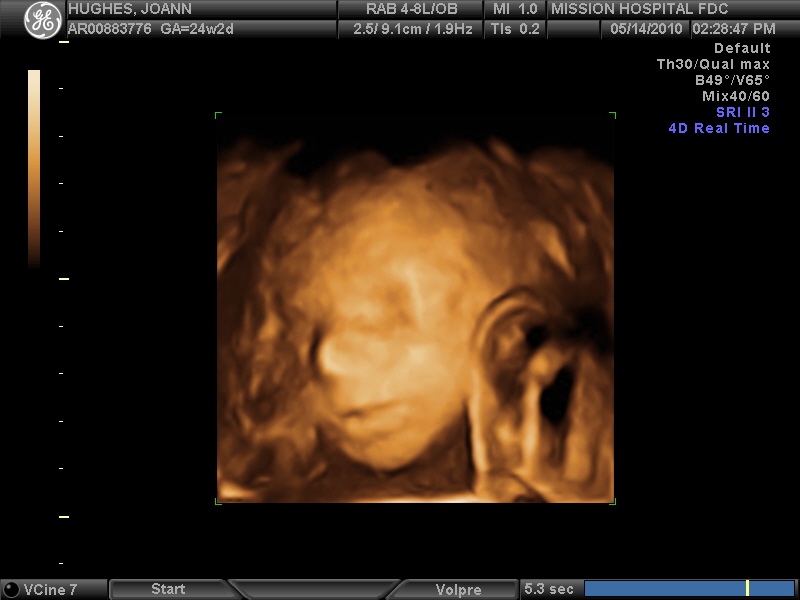

I have an AMAZING husband who I love and adore! We are living in California, where Casey owns/operates a Chick-fil-A restaurant! Haylee Ann Hughes blessed our lives on 9/2/10 with her arrival. We give God all of the glory for the many blessings in our lives.